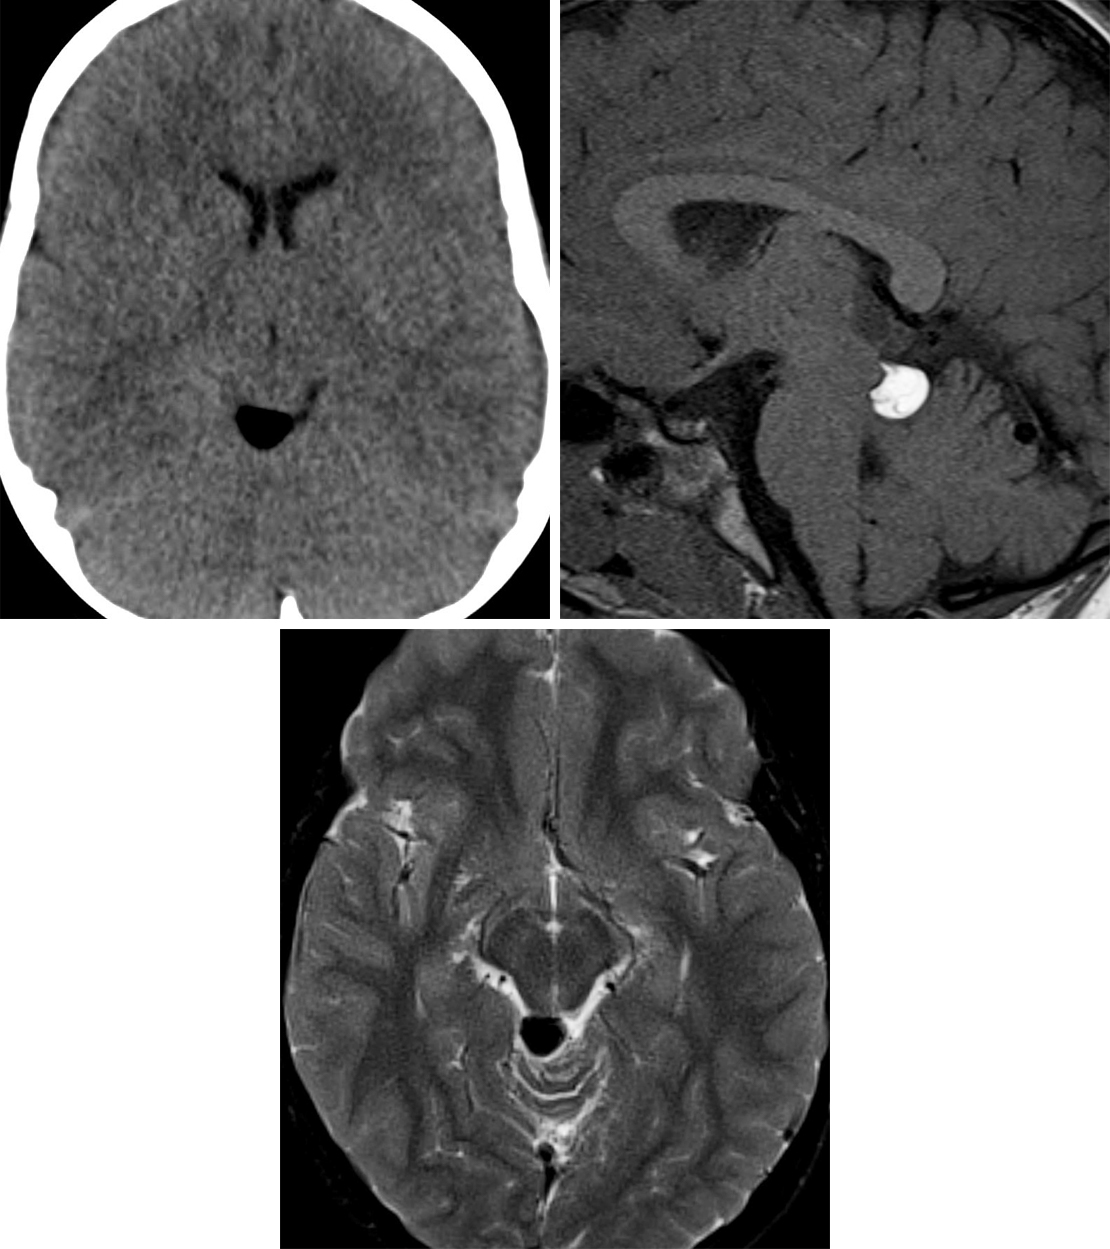

Quadrigeminal plate cistern lipoma. MRI demonstrates a mass in the …

Pericallosal lipoma – tubulonodular | Radiology Case | Radiopaedia.org …

📃 Lipoma of the corpus callosum

Intracranial Lipoma | The Neurosurgical Atlas